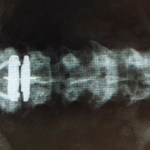

A comprehensive spinal evaluation includes a detailed assessment of your medical history, symptoms, physical examination, and diagnostic imaging, such as X-rays or MRIs. These diagnostic tools help doctors visualize the spine’s structure and identify any abnormalities that may be causing discomfort or pain. The evaluation may also include neurological tests to assess nerve function and determine if there is any nerve compression or damage.